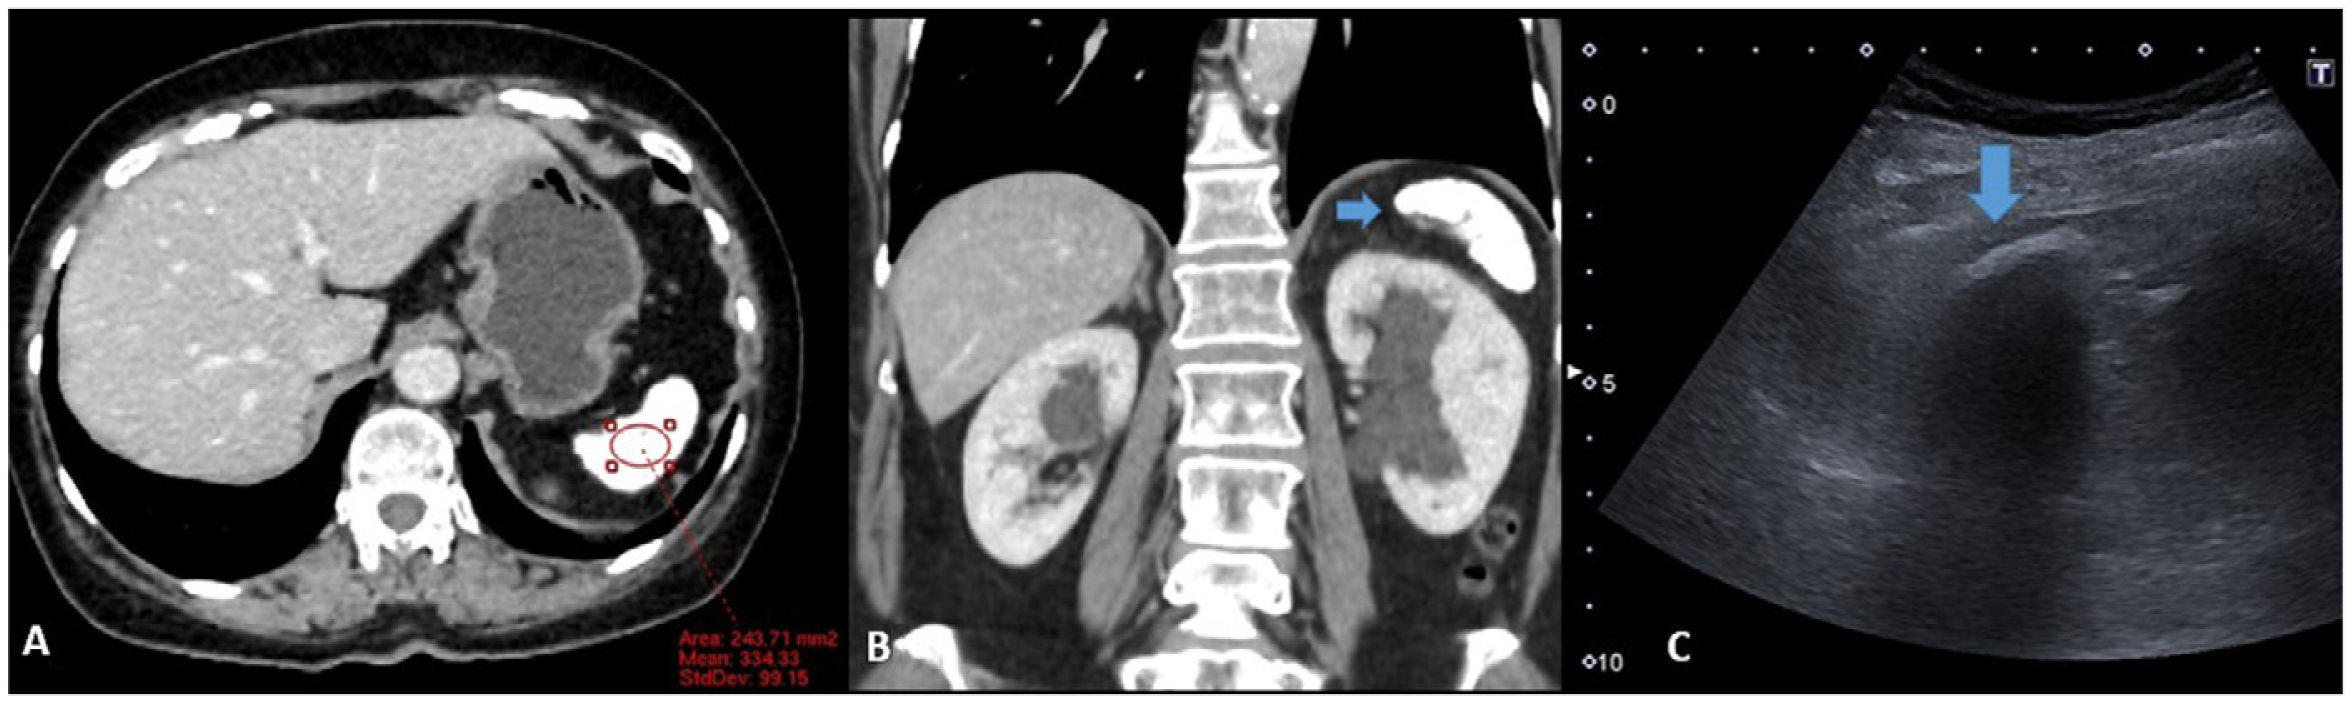

Radiología (English Edition) Thorotrast®: Lessons from the past for present radiological practice

Thorotrast®: Lessons from the past for present radiological practice

Thorotrast®: lecciones del pasado para la práctica radiológica del presente